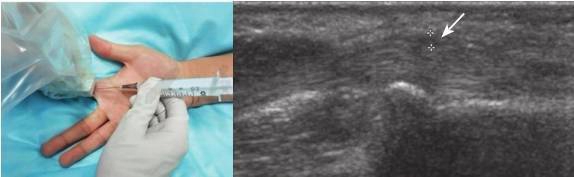

腱鞘由外层的腱纤维鞘和内层的腱滑膜鞘共同组成,具有固定、保护和润滑肌腱,使其免受摩擦或压迫的作用。肌腱在通过关节处长期过度摩擦即可发生腱鞘炎,部分炎性关节病患者如类风湿关节炎、痛风性关节炎等也可发生腱鞘炎。声像图上可表现为腱鞘增厚、回声减低、腱鞘积液,急性期者血流信号增加。对于症状明显者可选择超声引导下腱鞘内药物注射治疗,注射时选择肌腱短轴或长轴切面,采用平面内法进针(图13-5),目标区域为腱鞘增厚或积液处、肌腱表面,当针尖到靶区后缓慢推注适量局麻药与类固醇混合液,使药物在肌腱与腱鞘之间弥散分布。

图13-5 超声引导下扳机指治疗

箭:穿刺路径及药物注射部位;星号:增厚的A1滑车

对于狭窄性腱鞘炎包括桡骨茎突狭窄性腱鞘炎和扳机指,可联合使用针刺松解治疗(图13-5)。松解时选择肌腱长轴切面,在超声监视下针尖往返多次穿刺腱鞘增厚处或A1滑车,以扩张或松解增厚的腱鞘和A1滑车,减轻肌腱粘连卡压情况。松解后可主动或被动活动患指观察肌腱运动和弹响,病变严重者可分次进行松解治疗。进针前可人为地将穿刺针掰弯减小针体与皮肤表面的进针角度,在松解过程中使针体尽量与肌腱平行,利于松解增厚的腱鞘或A1滑车。